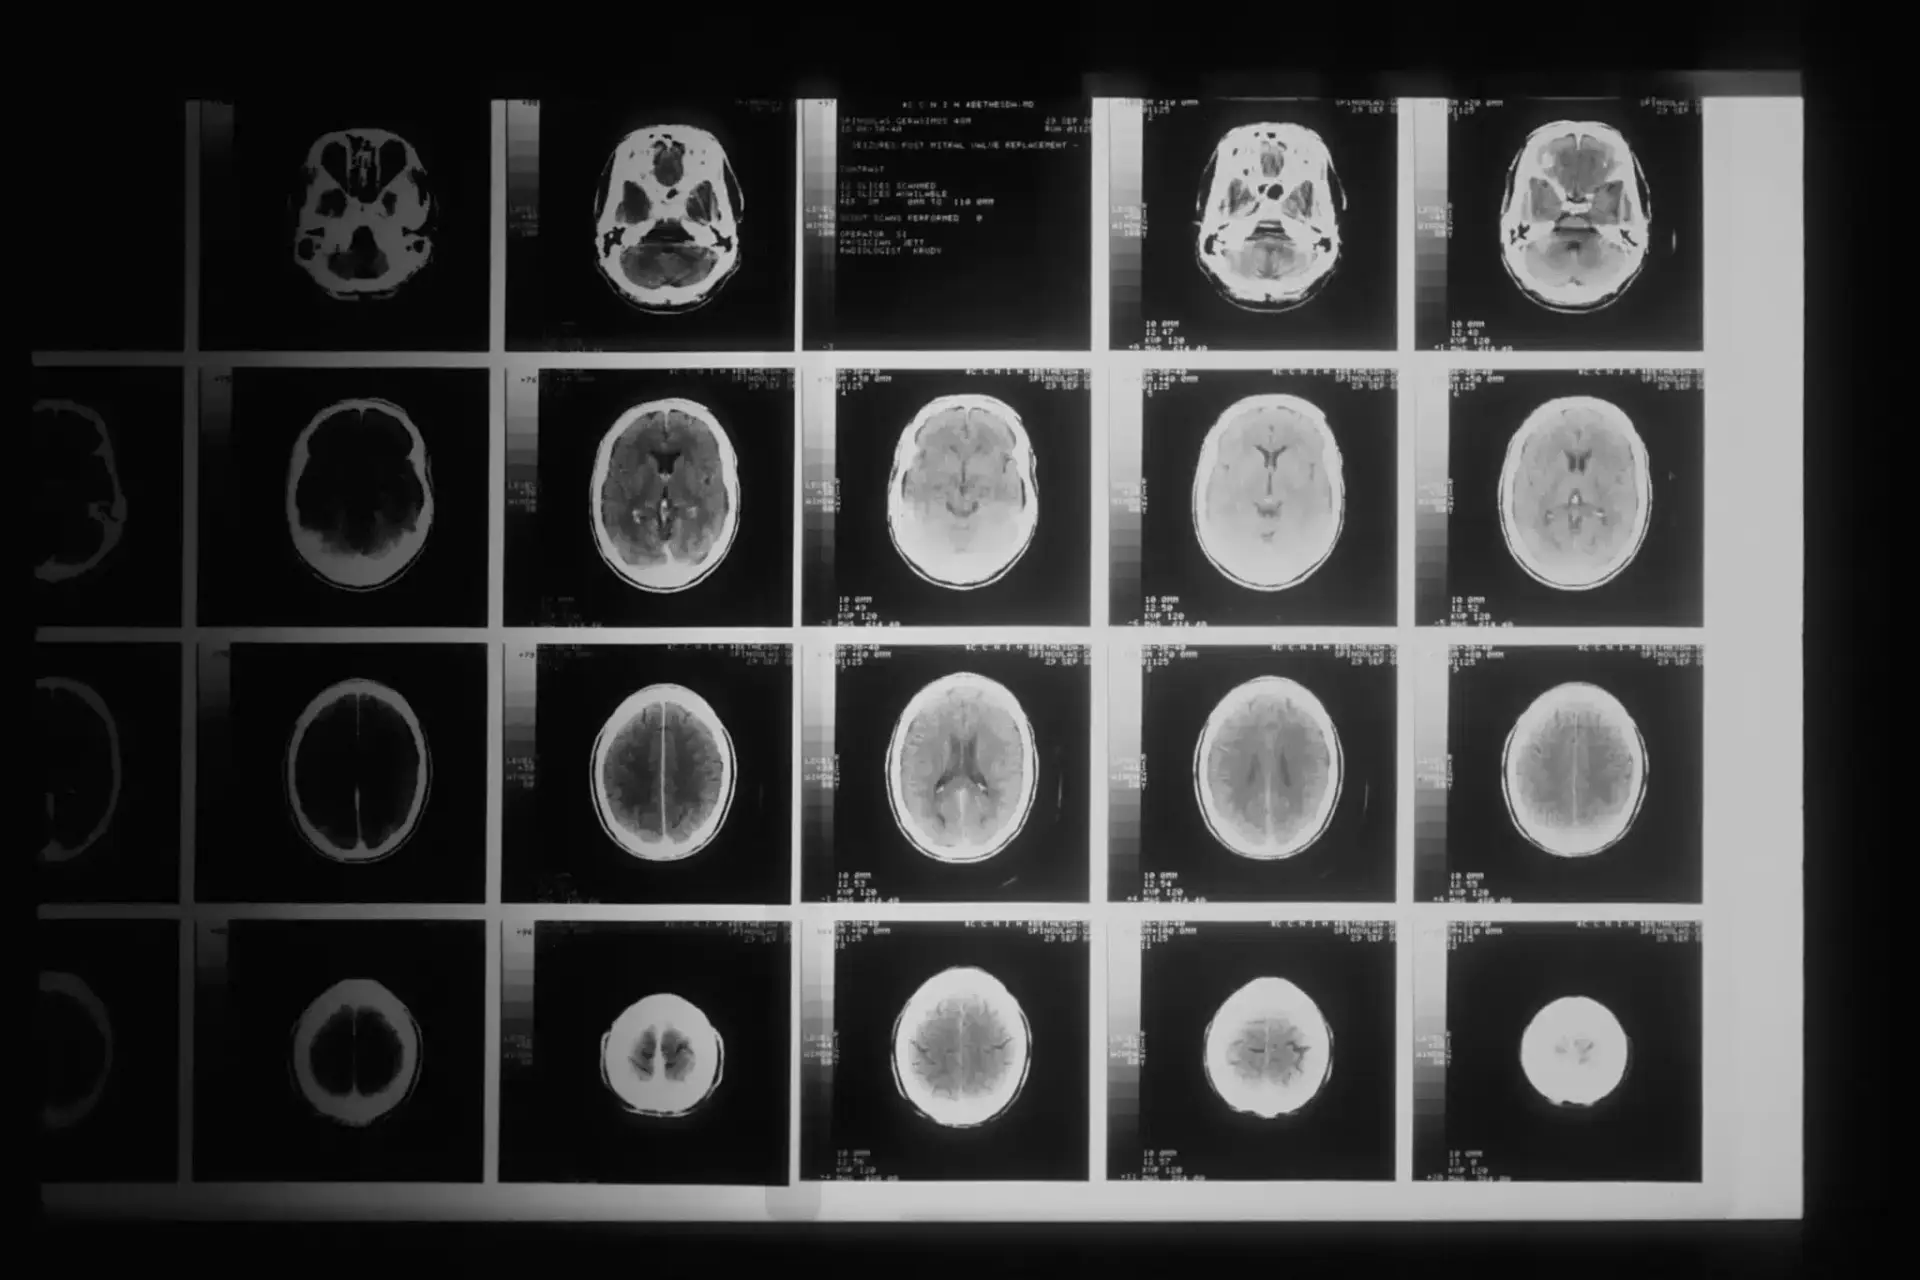

Everything You Need To Know About Blunt Force Head Trauma Blunt force head trauma is an injury that happens when a person’s head impacts a hard object or surface. For instance, victims may suffer blunt force head trauma in a motor vehicle collision or a slip and fall accident. Blunt force head trauma can cause harm […]

Blunt Force Head Trauma — Causes and Effects Blunt force head trauma is a leading cause of severe injury and often leads to lasting brain damage. Many situations can lead to this type of injury. When someone else is responsible for an accident that results in blunt force trauma, the responsible party — or their insurance provider […]

4 Types Of Brain Injuries And 3 Levels Of Severity If another person’s negligence caused you or a loved one to suffer a brain injury, you are likely confused about your rights and options for recovering compensation. Brain injuries can significantly impact a victim, potentially causing them to lose motor function and altering their personality. By learning about […]